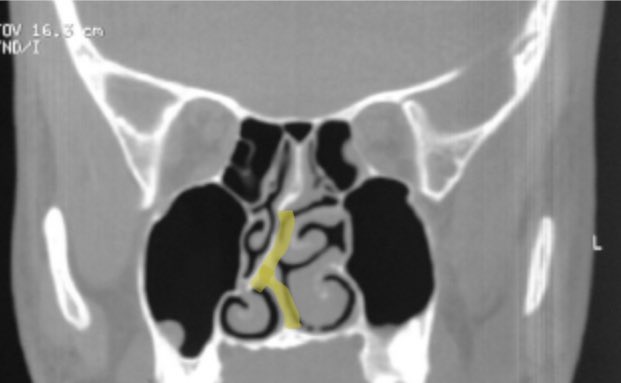

٥- الصداع الناجم عن نقاط الالتقاء : الانحراف الشديد في #الحاجز_الأنفي للدرجة التي تجعله يلامس #القرنيات_الأنفية المقابلة قد يسبب في حالات نادرة الصداع. عادة لا يتم تشخيص هذه الحالة الا بعد التأكد من عدم وجود أي سبب آخر يفسر الصداع ويكون العلاج بتعديل الحاجز الأنفي.